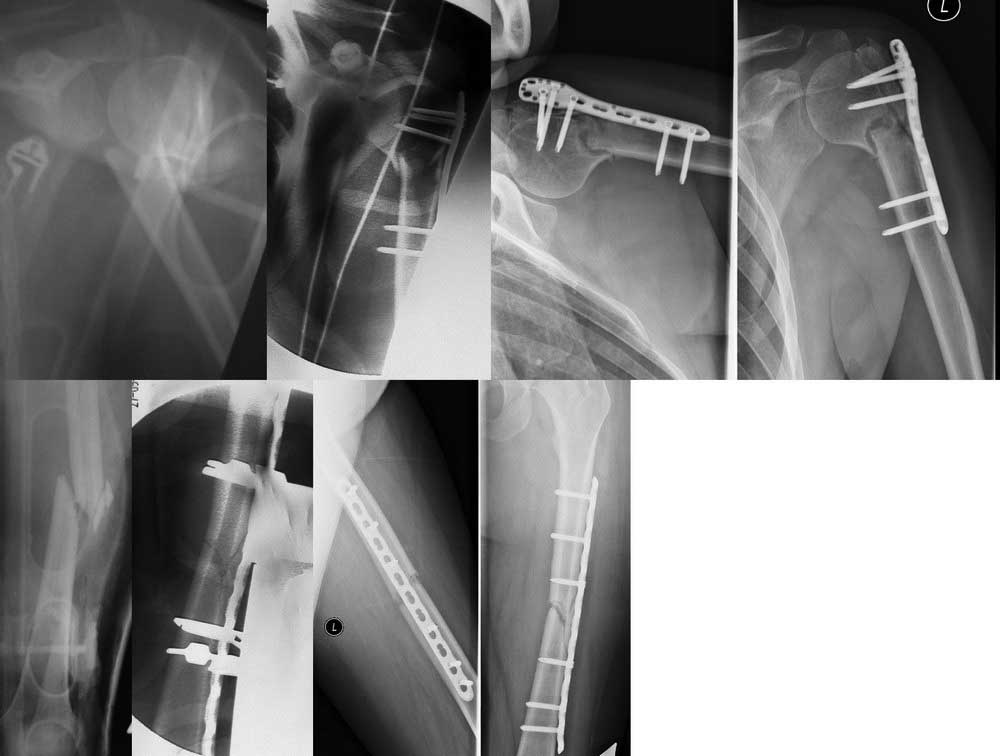

Женщина, 32 года. Травма от 17.09.2011г. в результате ДТП. При обследовании установлен диагноз: Сочетанная травма: ЗЧМТ. Сотрясение головного мозга. Закрытый оскольчатый перелом левой бедренной кости в средней трети со смещением отломков. Закрытый оскольчатый перелом хирургической верхней трети левой плечевой кости со смещением отломков.

27.09.2011г. выполнены операции: Открытая репозиция, металлоостеосинтез левой бедренной кости пластиной с угловой стабильностью винтов, левой плечевой кости проксимальной плечевой пластиной с угловой стабильностью винтов. Послеоперационный период без особенностей, раны зажили первичным натяжением, швы сняты на 14-е сутки.

27.11.2012г. выполнен рентгенконтроль, при которым определена положительная динамика консолидации перелома плечевой кости, начала ходить при помощи костылей без опоры на левую нижнюю конечность. На сегодняшний день ходит при помощи костылей с частичной нагрузкой на левую нижнюю конечность. Объём движений в левом коленном суставе восстановился полностью, в левом плечевом суставе сформировалась контрактура. При динамическом рентгеновском контроле определена картина замедленной консолидации.

В данный момент решаем вопрос об оперативном лечении. Сначала думаем выполнить плечо (смена фиксации на проксимальный гвоздь со стягивающими винтами и костной пластикой, либо костная пластика+проксимальная пластина), под той же анестезией выполнить туннелизацию области перелома бедренной кости. Далее по результатам этапного рентгенологического контроля по мере консолидации плечевой кости (и возможности ходить на костылях), в случае отсутствия положительной динамики на рентгенограммах принять решение о БИОС бедренной кости.

Снимки по хронологии слева направо: при поступлении-интраоперационно-на данный момент